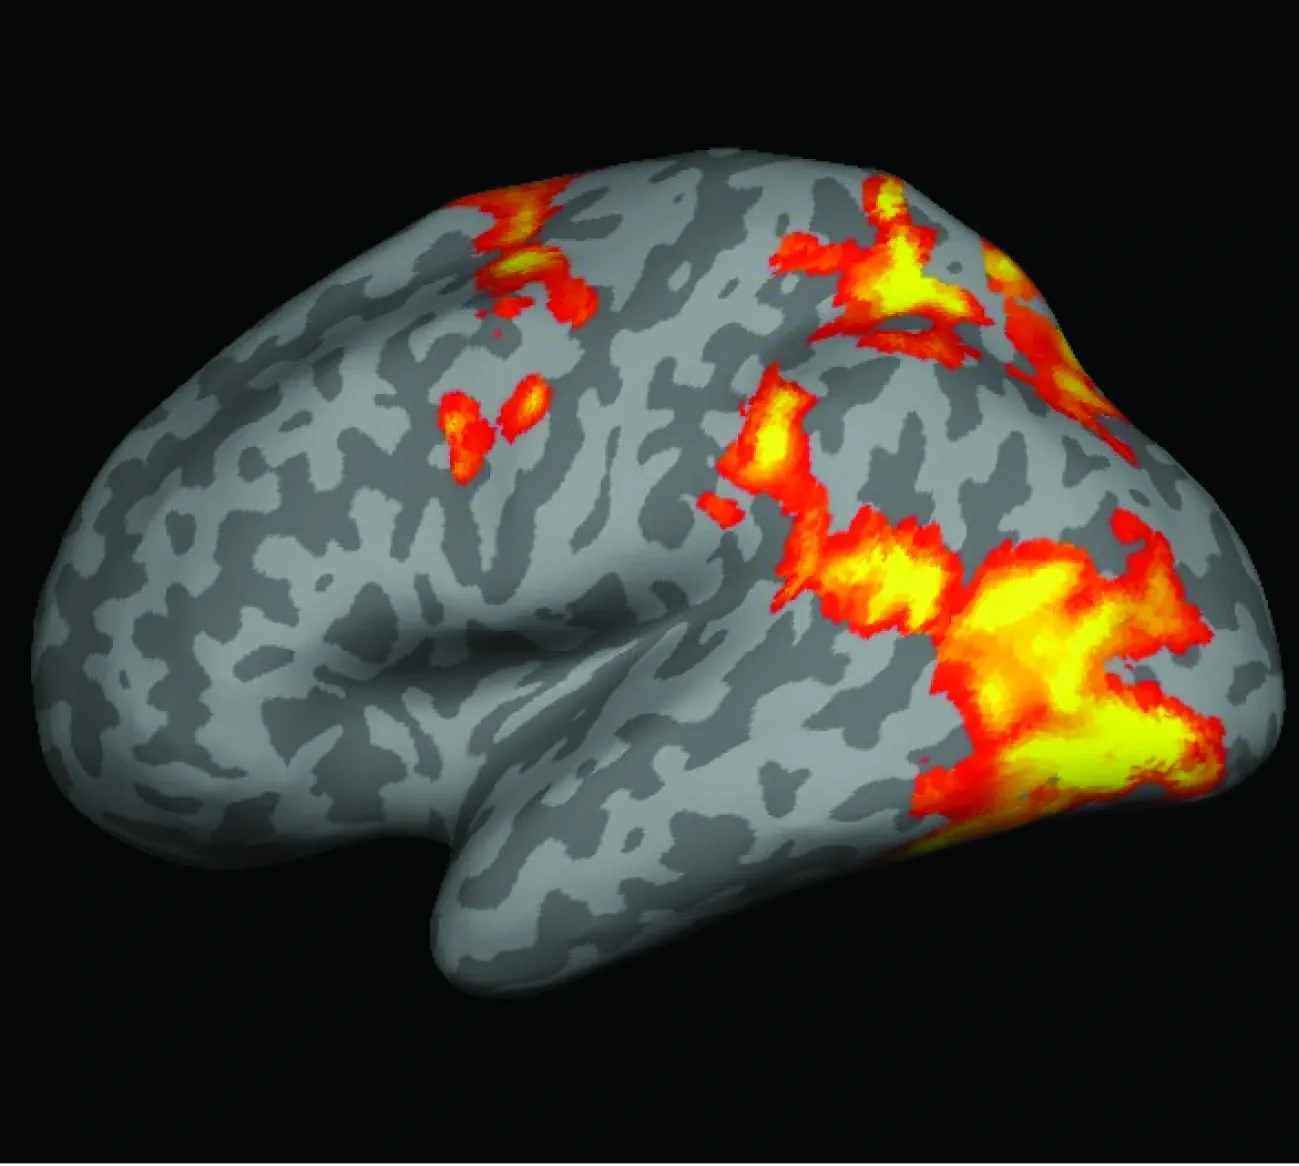

Combining behavioral and computational methods with functional magnetic resonance imaging (fMRI) has revealed how multisensory integration within premotor-posterior parietal and subcortical networks gives rise to body ownership, following probabilistic principles of perceptual inference. By integrating the spatial precision of fMRI with the millisecond temporal resolution of electroencephalography (EEG) and magnetoencephalography (MEG), we can characterize both where and when body-ownership computations occur in the brain. EEG experiments have shown that alpha-band oscillations constrain the temporal precision of sensory integration underlying bodily self-perception, while MEG has revealed how body-ownership-related activity patterns unfold dynamically across the brain with millisecond resolution.

Electrocorticography (ECoG), which provides high-quality neurophysiological signals from electrodes placed directly on the cortical surface in neurological patients, has linked the sense of limb ownership to increased high-gamma power—an index of local neuronal population firing—in premotor and posterior parietal cortex.

Brain stimulation with transcranial magnetic stimulation (TMS) and transcranial alternating current stimulation (tACS) allows us to perturb or modulate local brain activity at specific timings, oscillatory frequencies, or anatomical locations. These interventions affect behavioral markers of body-ownership perception and learning, enabling us to test causal mechanistic relationships between activity in premotor and posterior parietal regions and the computations underlying body-ownership experience.

Our neuroimaging studies have also demonstrated that body ownership and self-location depend on two interacting systems: lateral fronto-parietal circuits supporting body ownership and medial parieto-retrosplenial-hippocampal circuits supporting bodily self-location. Together, these systems give rise to the “in-body” experience of being located within one’s own body at a specific position in space.